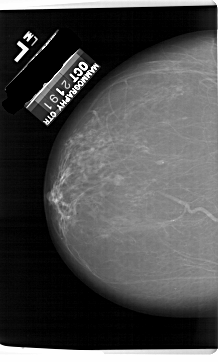

A_1632_1.RIGHT_MLO

RIGHT_MLO LINES 6466 PIXELS_PER_LINE 4171 BITS_PER_PIXEL 12 RESOLUTION 43.5 OVERLAY

FILE: A_1632_1.RIGHT_MLO.OVERLAY

TOTAL_ABNORMALITIES 1

ABNORMALITY 1

LESION_TYPE CALCIFICATION TYPE PLEOMORPHIC DISTRIBUTION CLUSTERED

ASSESSMENT 4

SUBTLETY 1

PATHOLOGY MALIGNANT

TOTAL_OUTLINES 1